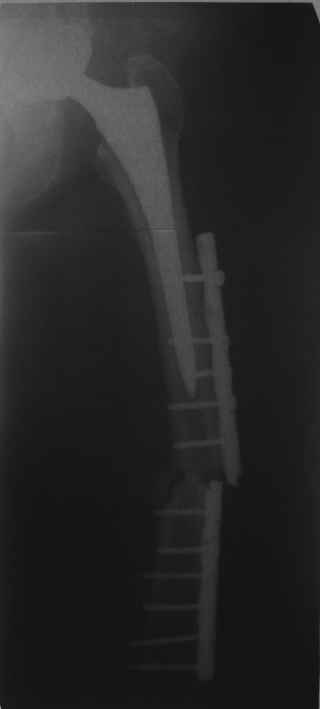

Уважаемые коллеги, в данном случае в лечении стандартного перипротезного перелома В2 Ванкуверской классификации (перелом вокруг ножки эндопртеза с потерей стабильности ножки при хорошем - не требующем пластики - качестве кости.Parvizi J, Rapuri VR, Purtill JJ, et al (2004) Treatment protocol for proximal femoral periprosthetic fractures. J Bone Joint Surg Am; 86-A Suppl 2:8-16)с успехом применён оригинальный, но малоизведанный способ лечения подобных повреждений. В результате и последующие рекомендации не могут быть стандартными. В подобных случаях, как это уже дискутировалось год назад, можно было выполнить ревизию длинной ножкой, во многом работающей как интрамедуллярный гводь + плюс кабель/серкляж в проксимальном отделе. Или, оставить имеющуюся ногу плюс длинная пластиа с кабелем/серкляжем, можно разными современными блокированными *примочками*. В таком случае при достижении консолидации пластина удаляется, тк при возникновении в будущем потребности в ревизии имеющийся дополнительный металл и без затруднит непростое вмешательство (кто пробовал, знает о чём я говорю). С длинной ногой, конечно, так же всё понятно. В данном случае мы имеем некую комбинацию, осложнённую отсутствием репозиции и фиксации в прошлом отломков вокруг ножки. Поэтому не каждый в данном случае рискнёт утверждать за счёт какого из компонентов системы - дистального либо проксимального обеспечивается стабильность. А если это и фиксация и за счёт ножки и за счёт гвоздя - каков баланс между данными компонентами в поддержании стабильности ситемы. То есть, я надеюсь, что дистального смещения ножки здесь не будет при условии сохранения как гвоздя, так и блокирующих винтов. При удалении же гвоздя возможна миграция ножки, только винтов - всей системы. Здесь же перелом (надеюсь, его не будет) блокирующих винтов может быть первым свидетельством механического неблагополучия системы... А так, помимо отличного результата этот случай так же косвенно подтверждает известную истину - Эндопротез, к сожалению, требует периодической замены. И выполняя фиксацию перипротезного перелома, а в последующем решая вопрос об удалении имплантатов, мы вынуждены думать и о функции сустава, и о том, как в будущем выполнить ревизию. Если ожидаемая продолжительность жизни пациента заставляет нас об этом думать. С уважением, Андрей

Как Вы знаете, мы имеем негативный опыт подобной операции (перелом ножки эндопротеза на месте соединения со штифтом), но тем не менее хотелось бы сказать следующее. На мой взгляд,выполняя такую фиксацию, мы становимся заложниками сохранения всей этой мегаконструкции на долгое время, если не на всю жизнь. Эта система работает уже как единое целое. Рефиксации ножки эндопротеза не произошло, при удалении гвоздя может развиться вторичная нестабильность, скорее всего со временем произойдут дистрофические изменения в кости за счет шунтирования нагрузки. Поэтому есть смысл отследить очень тщательно р-ты этих операций, прежде чем они войдут в повседневную практику, думаю что показания к ним будут весьма ограничены. Пару раз попробовали "пошалить", собрали бедро на бесцементной ножке у пожилых б-х дабы не утяжелять вмешательство. В одном случае - срослось и ножка получила стабильность, в другом - потребовалось реэндопротезирование, но со значительно меньшей травмой. т.к.бедро срослось.

Сейчас опорную нагрузку на бедро берет на себя система от бедренного компонента эндопротеза до проксимального винта в интрамедуллярном гвозде. Свидетельство тому - реакция кортикала утолщением вокруг того самого винта. Таким образом вся кость от верхушки б.вертела до проксимального винта не испытывает физиологической осевой нагрузки. Результатом этого могут стать следующие последствия друг друга не исключающие: 1) все будет хорошо до перелома опорной системы по винту(ам) или в месте соединения штифта с ножкой или еще где-либо, 2) исключенная из-под нагрузки кость будет терять в количестве и качестве, что не очень (или очень не) хорошо для возможных будущих ревизий (тьфу-тьфу!!!).